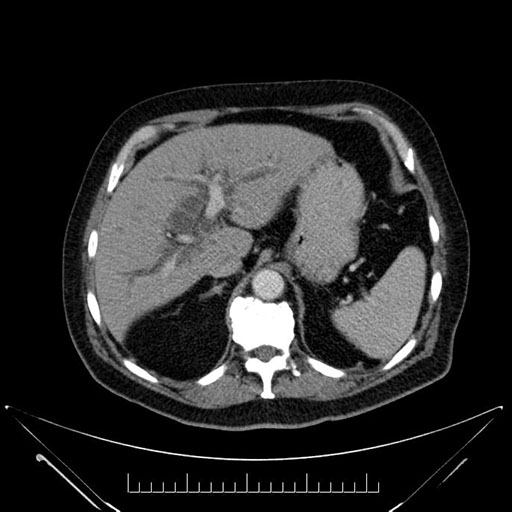

Axial - stented